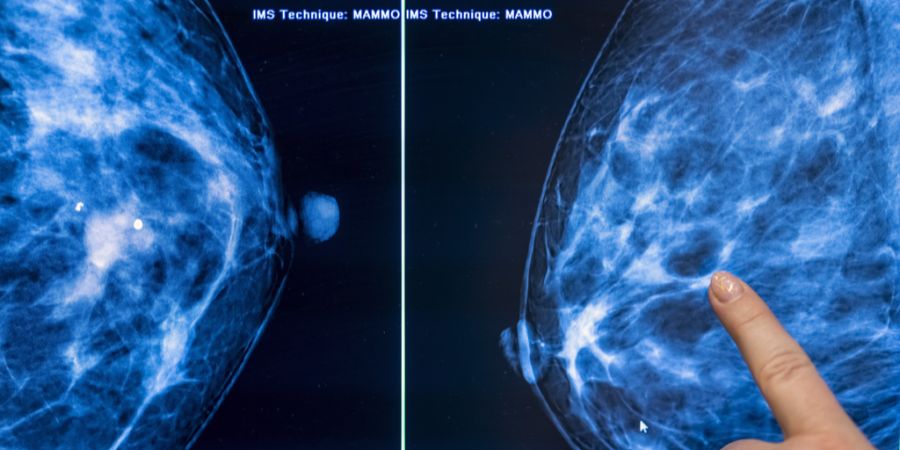

Roche meldet bedeutende Fortschritte mit dem Mittel Giredestrant. In einer Studie zeigte es deutliche Wirkung bei Hormonrezeptor-positivem Brustkrebs.

In der zulassungsrelevanten Studie «Lidera» habe das Mittel Giredestrant sämtliche vordefinierten Endpunkte erfüllt, so der Pharmakonzern. Laut «Reuters» verlängerte das Medikament das progressionsfreie Überleben von Brustkrebspatientinnen signifikant.

Roche untersucht den Wirkstoff als sogenannten oralen selektiven Estrogenrezeptor-Degrader. Laut dem «SRF» richtet sich die Studie an Frauen mit fortgeschrittenem oder metastasiertem Brustkrebs, der auf Standardtherapien nicht mehr anspricht.